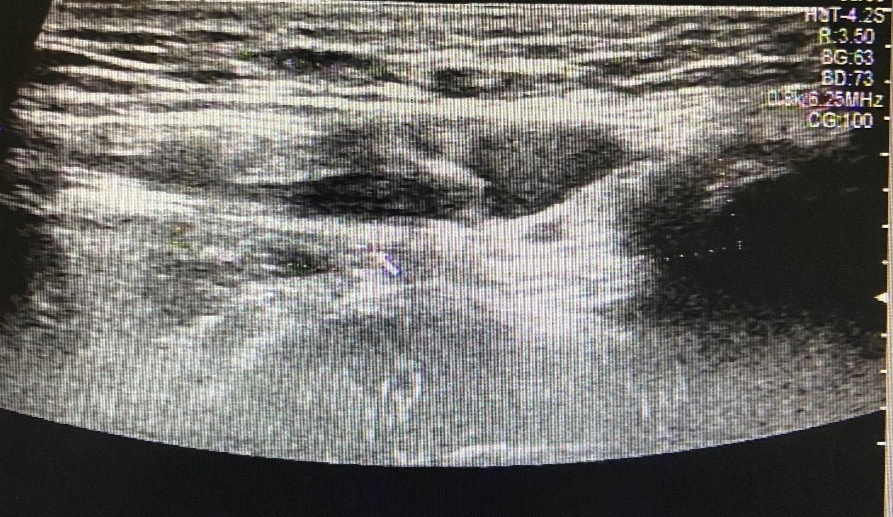

图片

图 2 左侧腹股沟区包块

超声所见

左侧腹股沟区见范围约 4.4cm×3.2cm×2.0cm 无回声区,可见少量分隔,增减腹压大小无明显变化。右侧腹股沟区未见明显异常回声。

超声提示

左侧腹股沟无回声区,子宫圆韧带囊肿?积液?

术后证实为左侧子宫圆韧带囊肿。